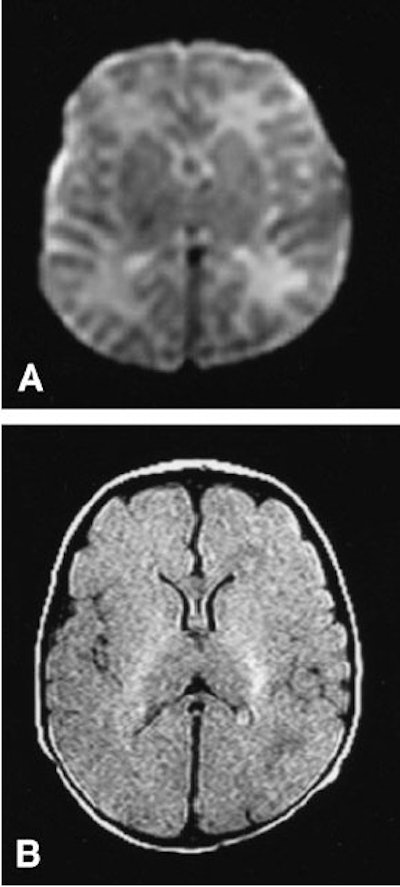

![]() |

| Images from a normal study of a premature neonate born at 30 weeks' gestation, and imaged 19 days after delivery. Diffusion-weighted image (A); FLAIR image (B). Ultrafast Magnetic Resonance Imaging of the Neonate in a Magnetic Resonance-Compatible Incubator With a Built-In Coil, Whitby EH, Griffiths PD, Lonneker-Lammers T, Srinivasan R, Connolly DJA, Capener D, Paley MNJ, Pediatrics, February 2004, Vol.113, No.2, p.e151. |

The group reported good or excellent T1- and T2-weighted images, diffusion-weighted images, and FLAIR images in all seven cases. The neonates remained stable throughout the exams. They found three of the babies to be normal, three with subdural hematoma, and one with germinal matrix hemorrhage.